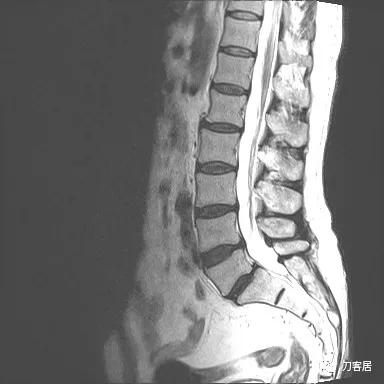

图11. 20210626术前腰椎MRIT2相1

图12. 20210626术前腰椎MRIT2相2

入院后予以腰椎CT及MRI检查,未见明显之椎间盘突出及椎管狭窄。